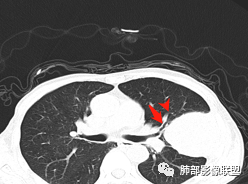

老年男性,外伤入院,“左上肺”实性肿块,边缘光滑,突破壁层胸膜并侵犯肋骨及肋间肌,增强扫描轻度强化,可见明显坏死。

• 患者老年男性,因摔伤致腰部、双侧髓部疼痛2月余就诊

• 胸CT:左肺上叶实性占位,病灶与支气管无关,病灶对斜裂挤压,病灶周围光滑,未见分叶、毛刺;纵隔窗可见病灶内低密度区,病灶对胸壁侵袭,并可见肋骨破坏。

左肺上叶下舌段胸膜下肿块,宽基底与胸膜相连,尖端指向肺门,病变呈膨胀性生长,边缘有清晰的GGO,病灶下缘似有空泡,病灶外缘向胸壁外侵犯(有栽赃),局部肋骨有破坏,平扫密度均匀,增强后轻度强化,中老年男性,有外伤史,考虑恶性,神经鞘瘤,恶性肉瘤,恶性孤立性纤维瘤,鉴别血肿(强化不太符合)

胸部CT所见左肺上叶尖后段胸膜下较大山丘形肿块,边界清楚,宽基底与胸膜相贴,边缘与胸膜呈直角及锐角相交。邻近上叶尖后段支气管受压推挤,叶裂局部膨隆,病灶周围见少许磨玻璃密度影,边界不清。纵膈窗显示,肿块密度均匀,增强扫描呈不均匀轻度强化,邻近肋骨骨质破坏,病变沿肋间隙向外侵犯,局部胸膜增厚。纵膈内见多发小淋巴结,未见胸腔积液征象。综合考虑恶性占位,肉瘤样癌可能性大。腰椎及髋部考虑骨转移。